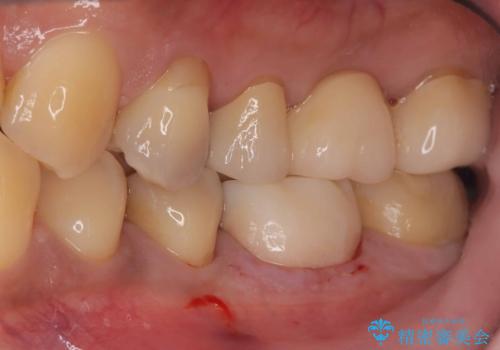

- 銀歯2本の下が虫歯になっていたので、フルジルコニアクラウンとセラミックインレーで治療を行いました。

適合が良い被せ物を入れるために、歯の境としっかり合わせた仮歯を入れ、歯茎の状態を良くしてからシリコンで型取りをしています。